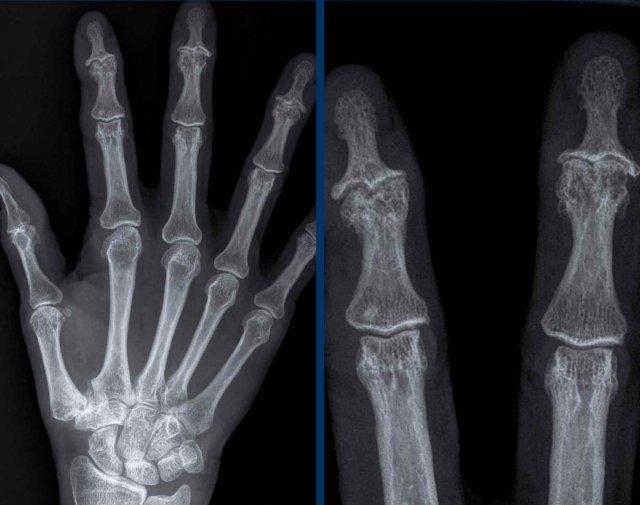

Viêm khớp nhiễm khuẩn tại khớp liên đốt gần (PIP) ngón 3.

Có phù nề mô mềm rất lớn tại ngón 3.

Có các bào mòn lan rộng tại khớp kèm theo một số mảnh xương nhỏ.

Viêm khớp nhiễm trùng là biến chứng của áp-xe đầu ngón tay.

Các dấu hiệu bao gồm:

- Phù nề mô mềm

- Bào mòn và hẹp khe khớp liên đốt xa (DIP).

- Xơ cứng dưới sụn và hình thành gai xương là do thoái hóa khớp thứ phát.